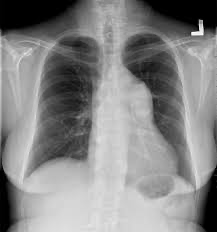

정상 Xray

Xray : mild cardiomegaly, 폐혈관 음영 증가